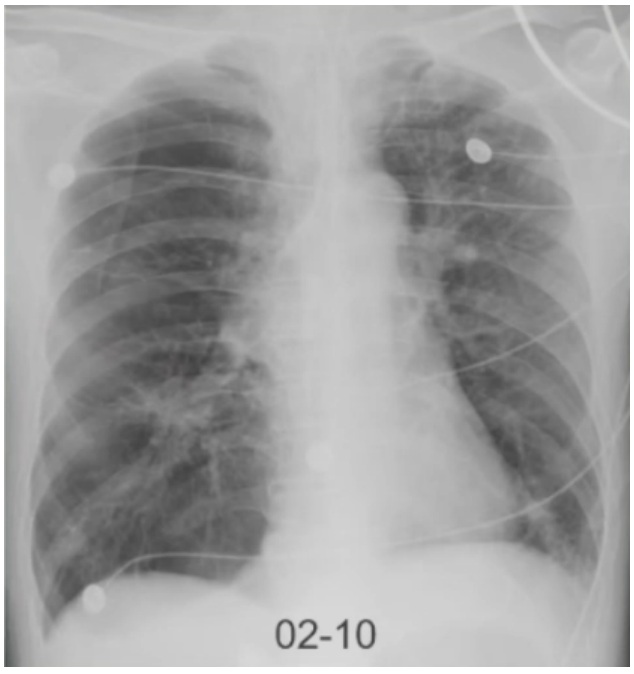

- 胸部CT:左侧气胸,肺气肿,肺大泡,两肺结节较前相仿(图1)。

慢性阻塞性肺疾病(急性加重期,极重度);肺性脑病;Ⅱ型呼吸衰竭;呼吸性酸中毒;左侧自发性气胸(肺压缩15%);肺诊断性影像学异常。